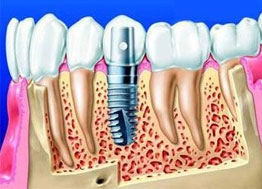

| 几乎适用所有缺牙类型 | 必须两侧邻牙健康、无缺失 | 几乎适用所有缺牙类型 | ||

| 无伤害 - 不磨损健康邻牙 强功能 - 咀嚼如真牙 更美观 - 色比真牙 |

需要磨掉旁边两颗邻牙 | 影响发音、恶心,咀嚼功能不佳 | ||

| 40年以上 | 10-20年 | 3-5年 | ||

| 正常清洁检查 | 定期复查还需注意咀嚼时避免用力过大 | 使用年限不长,容易老化变形 |